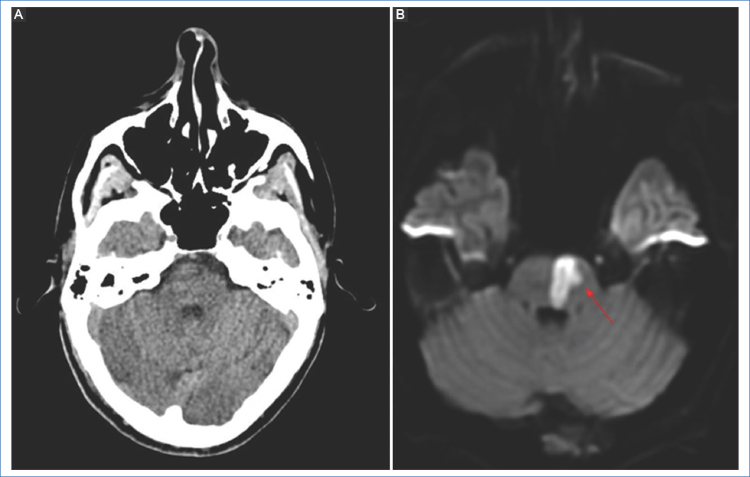

Dentro del espectro de los estudios por imágenes, la tomografía computada (TC) con angiotomografía computada (angio-TC) es de amplia disponibilidad y permite visualizar algunos signos tempranos de isquemia y la presencia de hemorragias; sin embargo, posee una baja sensibilidad para la detección de pequeñas lesiones isquémicas, sobre todo las ubicadas en la fosa posterior o bien lesiones corticales focales2 (Fig. 1).

DWI y mapa de ADC

Luego de la oclusión vascular comienza una cascada de eventos, como la falla de la bomba de sodio y potasio, aumento del calcio intracelular, despolarización celular, generación de radicales libres, inflamación y apoptosis, produciendo edema intracelular (citotóxico) y disminución del movimiento browniano de los líquidos4. Dentro de la evaluación del parénquima cerebral, la secuencia DWI y el mapa de coeficiente de difusión aparente (ADC, por sus siglas en inglés), son las que presentan mayor sensibilidad para la detección de isquemia parenquimatosa, con una sensibilidad del 88-100% y especificidad del 95% para detectar el core del infarto, en relación con la TC5,6, aunque hay un pequeño número de pacientes en los cuales no se observan alteraciones (stroke DWI-negativo)6. La anormalidad de señal en la secuencia DWI (representando el edema citotóxico) se observa hiperintensa y corresponde a una restricción en la difusión normal de la molécula de agua dentro del parénquima encefálico, con la equivalente reducción de los valores de ADC (hiposeñal). Esto representa signos de lesión irreversible y corresponde al core del infarto7 (Fig. 1). La reducción de los valores del coeficiente de difusión en el mapa de ADC pueden observarse a los 30 minutos luego del comienzo de la isquemia, alcanzando valores más bajos alrededor de los 3-5 días. Luego los valores de ADC comenzarán a incrementarse, hasta alcanzar una pseudonormalización alrededor de las 2-4 semanas, debido al mayor componente vasogénico del edema, en vez de citotóxico (efecto T2 shine through)2,7.